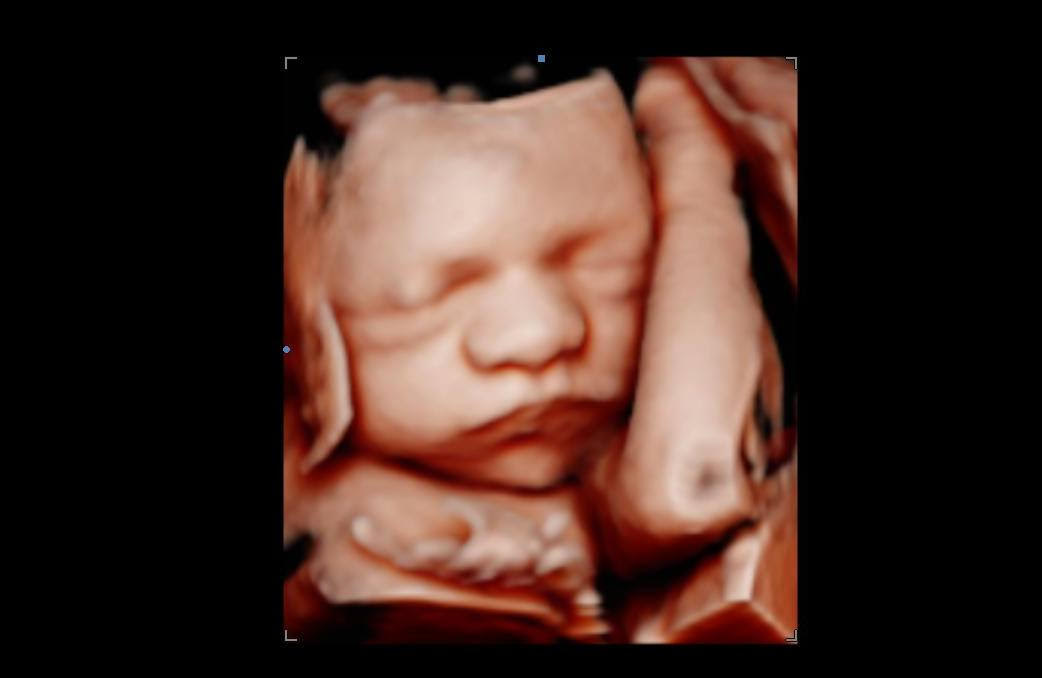

Real 4D and HD Ultrasound Photos from Knoxville, TN Families

Every photo in this gallery is a real image captured during an elective ultrasound session at Behind the Bump HD in Knoxville, TN. These are genuine keepsake moments from families just like yours, not stock photos or samples from other studios. When you book with us, you are booking the same care, the same equipment, and the same unhurried approach that produced every image you see here.

Browsing our 4D ultrasound photos gives you a clear idea of what your session can look like. You will see a range of images, from early 2D visits and gender reveal moments to rich 3D, 4D, and HD live facial detail captured during the most popular weeks between 26 and 32 weeks. Babies are unpredictable, but we have spent many sessions helping families get those sweet expressions, tiny stretched arms, and peaceful faces that you will want to hold onto for years.